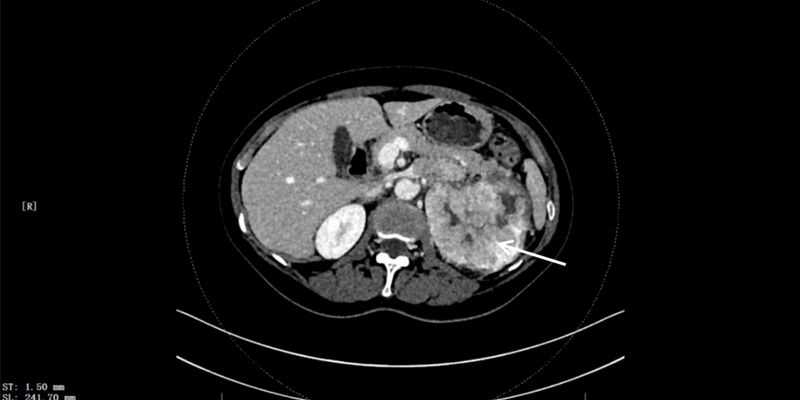

美国FDA授予新型PET显像剂ITM-94快速通道资格,为透明细胞肾细胞癌(RCC)的诊断带来新突破。临床数据显示,ITM-94能精准识别原发灶及常规影像难以发现的转移灶,且安全性高。了解这一创新诊断工具如何改变RCC的诊疗决策,并为其治疗药物ITM-91的开发铺平道路。 Read More... "透明细胞肾细胞癌(RCC)诊断新突破:ITM-94显像剂获FDA快速通道资格"